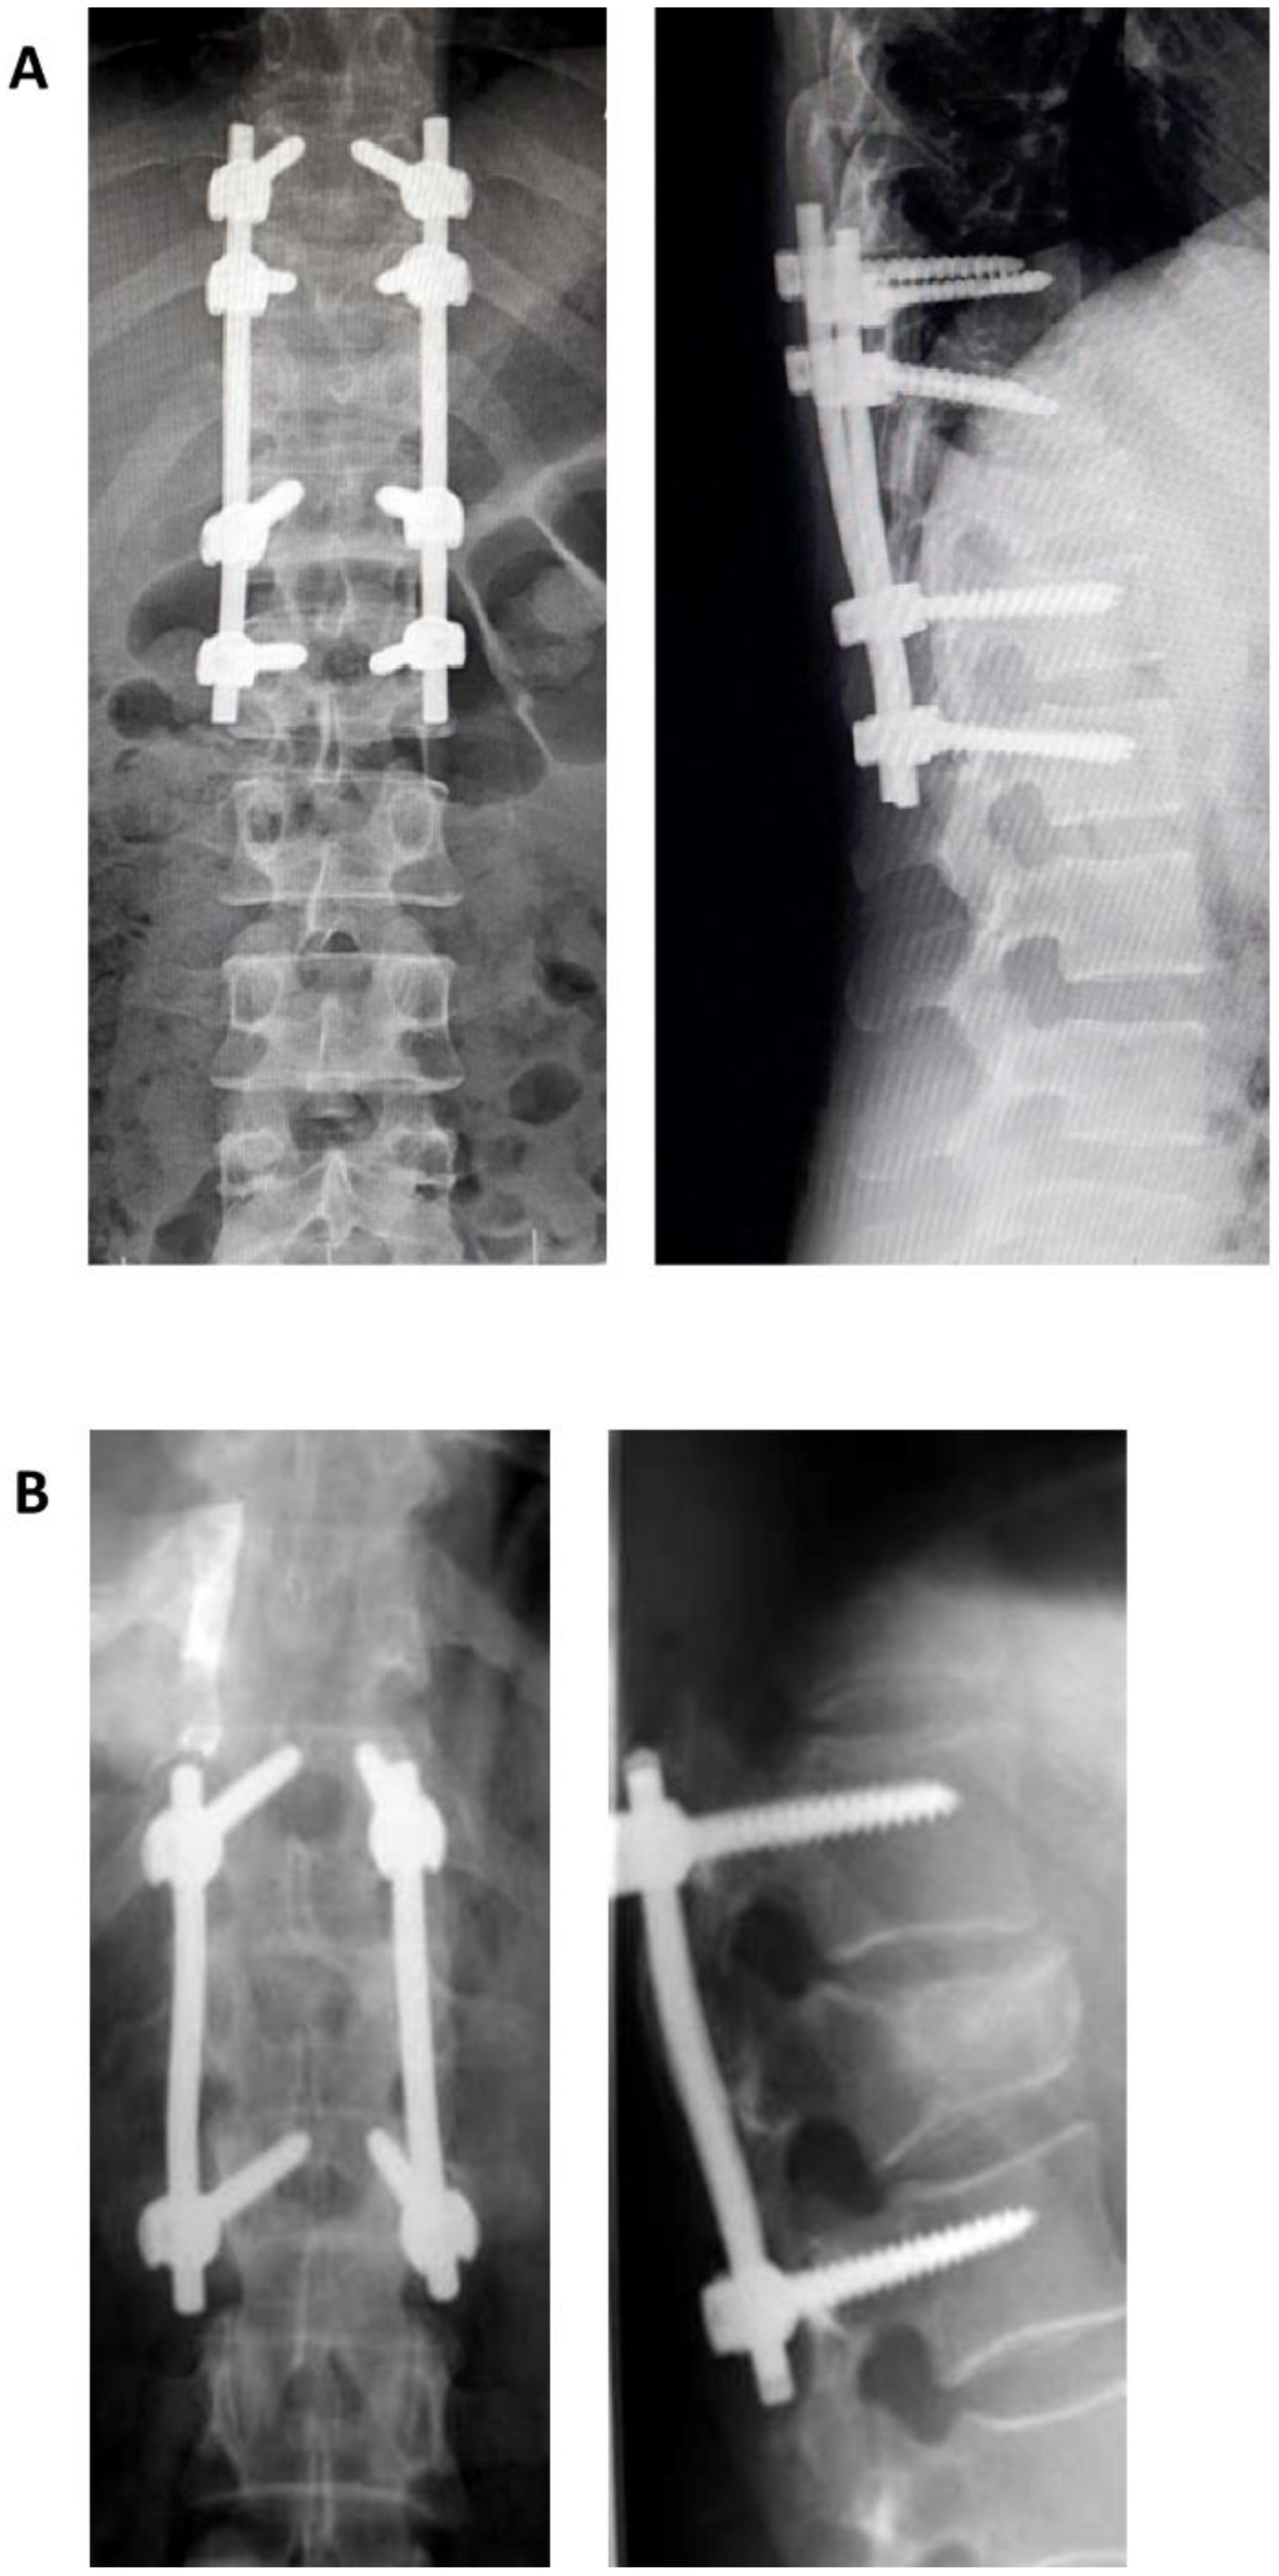

3. The Load Sharing Classification (LSC) of Spine Fractures

A classification based on a quantitative point system, The Load Sharing Classification (LSC) of Spine Fractures was published by McCormack and Gaines in 1994 [18]. This classification appeared as a result of the increasingly extensive use of pedicular screws, a technique described and used by Roy Camille, initially in spine fractures, then in other types of spinal pathologies [19,20,21,22,23]. The authors documented in certain cases the failure of short segment pedicular screws SSPS instrumentation systems—of one level above, or one level below—used for the treatment of three-columns fractures and fractures–dislocations in the thoracic and thoracolumbar areas, leading to kyphosis. This classification evaluates, based on a quantitative point system, the following elements: (1) the degree of kyphosis correction on lateral view, (2) degree of vertebral body comminution, (3) the apposition of the fracture fragment. Each element can be evaluated with 1 to 3 points, leading to an overall score of 3 to 9. As the score increases, the anterior support is more severely affected. SPSS is indicated for a score of 6 or lower. For a score greater or equal to 7, without dislocation (severe burst fractures) short-segment anterior corpectomy, strut-graft fusion and instrumentation is indicated. If dislocation is also present then, for the same score of 7 or greater, SPSS followed by an anterior approach (circumferential, 360 degrees) is indicated. Alternatively, LSPS (8 screws) can be used with the downside of supplemental mobility impairment. The authors underline from the beginning a couple of disadvantages of their classification such as a lack of evaluation of the mechanism of injury, ligament integrity, which in turn makes this score unusable for surgical decision making (the evaluation of the ligamentous system is essential in therapeutical decision). In conclusion, this classification is useful in making the choice between SSPS or LSPS, as well as the anterior approach (Figure 1).

Figure 1. Postoperative X-ray showing a long segment pedicular screws (A) and short segment pedicular screws (B).